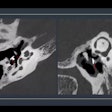

Revealed: The cause of CT safety incident in Belgium